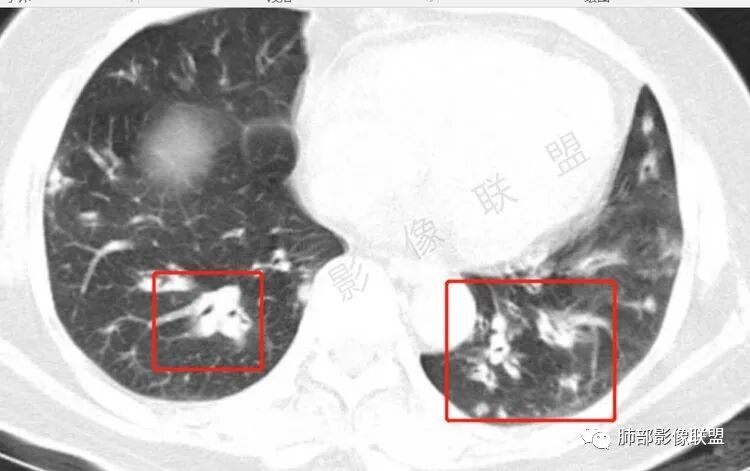

胸CT:双中下肺支气管壁明显增厚,双下肺胸膜下可见实变区。部分病变呈楔形影。

老年女性,咳嗽咳痰低热20天,双肺野散在结节影,随机分布,双肺下叶支气管血管束增粗,支气管管腔狭窄,胸膜下结节斑片影,临床有血尿,痰培养白念阳性,低氧血症。血管炎抗体阴性。从影像看主要侵犯的是血管,血管壁增厚,血管炎抗体阴性不大支持,患者有血尿,考虑膀胱肿瘤引起转移,但是膀胱彩超没发现占位,估计血尿是膀胱炎引起。从影像看考虑侵袭性曲霉菌病?血管炎?实在没有思路。

双肺多发大小不等结节,周围伴有晕征,边界模糊,部分结节内似可见支气管影,双肺血管束明显比支气管增粗,临床有感染症状,考虑GPA,疱疹病毒。

双肺支气管管壁弥漫性增厚,管腔狭窄,下叶为主,伴多发高密度结节影,边缘模糊,双肺支气管血管束明显增粗,临床症状咳嗽低热,有血尿,首先考虑血管炎

影像上:多发结节沿血管分布;双下叶支气管血管束简直增厚,偏血管,支气管通畅

因为支气管壁增厚,远端应该小气道病变,这个不是,反而是血管增粗明显

加上结节的分布,支持血管相关病变

两肺多发结片影,这个病灶很小,但是中间可见支气管影,支气管炎一般不会包在支气管周围,支气管周围间质可能大,包括血管,淋巴等。一般支气管这样穿行的,被包绕的,血管炎,淋巴瘤等这种间质起源比较多见